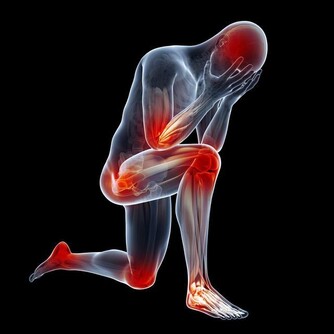

年齡漸長,發生骨質疏鬆的機會也跟著增加。(網絡圖片)

隨著年齡漸長,發生骨質疏鬆的機會也跟著增加,往往一不注意就落入骨質脆弱的環節里。